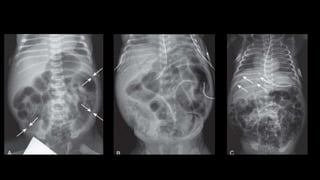

Doença de Hirschsprung

• 1 – 5000 nascidos

• Falha na migração distal das células da crista neural do nervo vago

• Migração porém sem capacidade de se proliferar

• Meninos:meninas 4:1

• Trissomia do 21 e outras anomalias de migração neural.

• Waardenburg, Shprintzen-Goldberg, McKusickKaufman, Bardet-Biedl,

Currarino syndrome e síndrome de Haddad.

• Apresentação clínica neonato

• Obstrução distal – distensão abdominal e vômitos biliosos

• Falha na passagem do mecônio nas primeiras 24hr

• Crianças

• Constipação, distensão abdominal, vômitos.

• Associação com enterocolite – constipação X diarreia

4 anos

• Razão retossigmoide < 0,9

• Aganglionose total do cólon

Doença de Hirschsprung •1 – 5000 nascidos • Falha na migração distal das células da crista neural do nervo vago • Migração porém sem capacidade de se proliferar • Meninos:meninas 4:1 • Trissomia do 21 e outras anomalias de migração neural. • Waardenburg, Shprintzen-Goldberg, McKusickKaufman, Bardet-Biedl, Currarino syndrome e síndrome de Haddad.

Doença de Hirschsprung •Apresentação clínica neonato • Obstrução distal – distensão abdominal e vômitos biliosos • Falha na passagem do mecônio nas primeiras 24hr • Crianças • Constipação, distensão abdominal, vômitos. • Associação com enterocolite – constipação X diarreia 4 anos

Doença de Hirschsprung •Razão retossigmoide < 0,9 • Aganglionose total do cólon